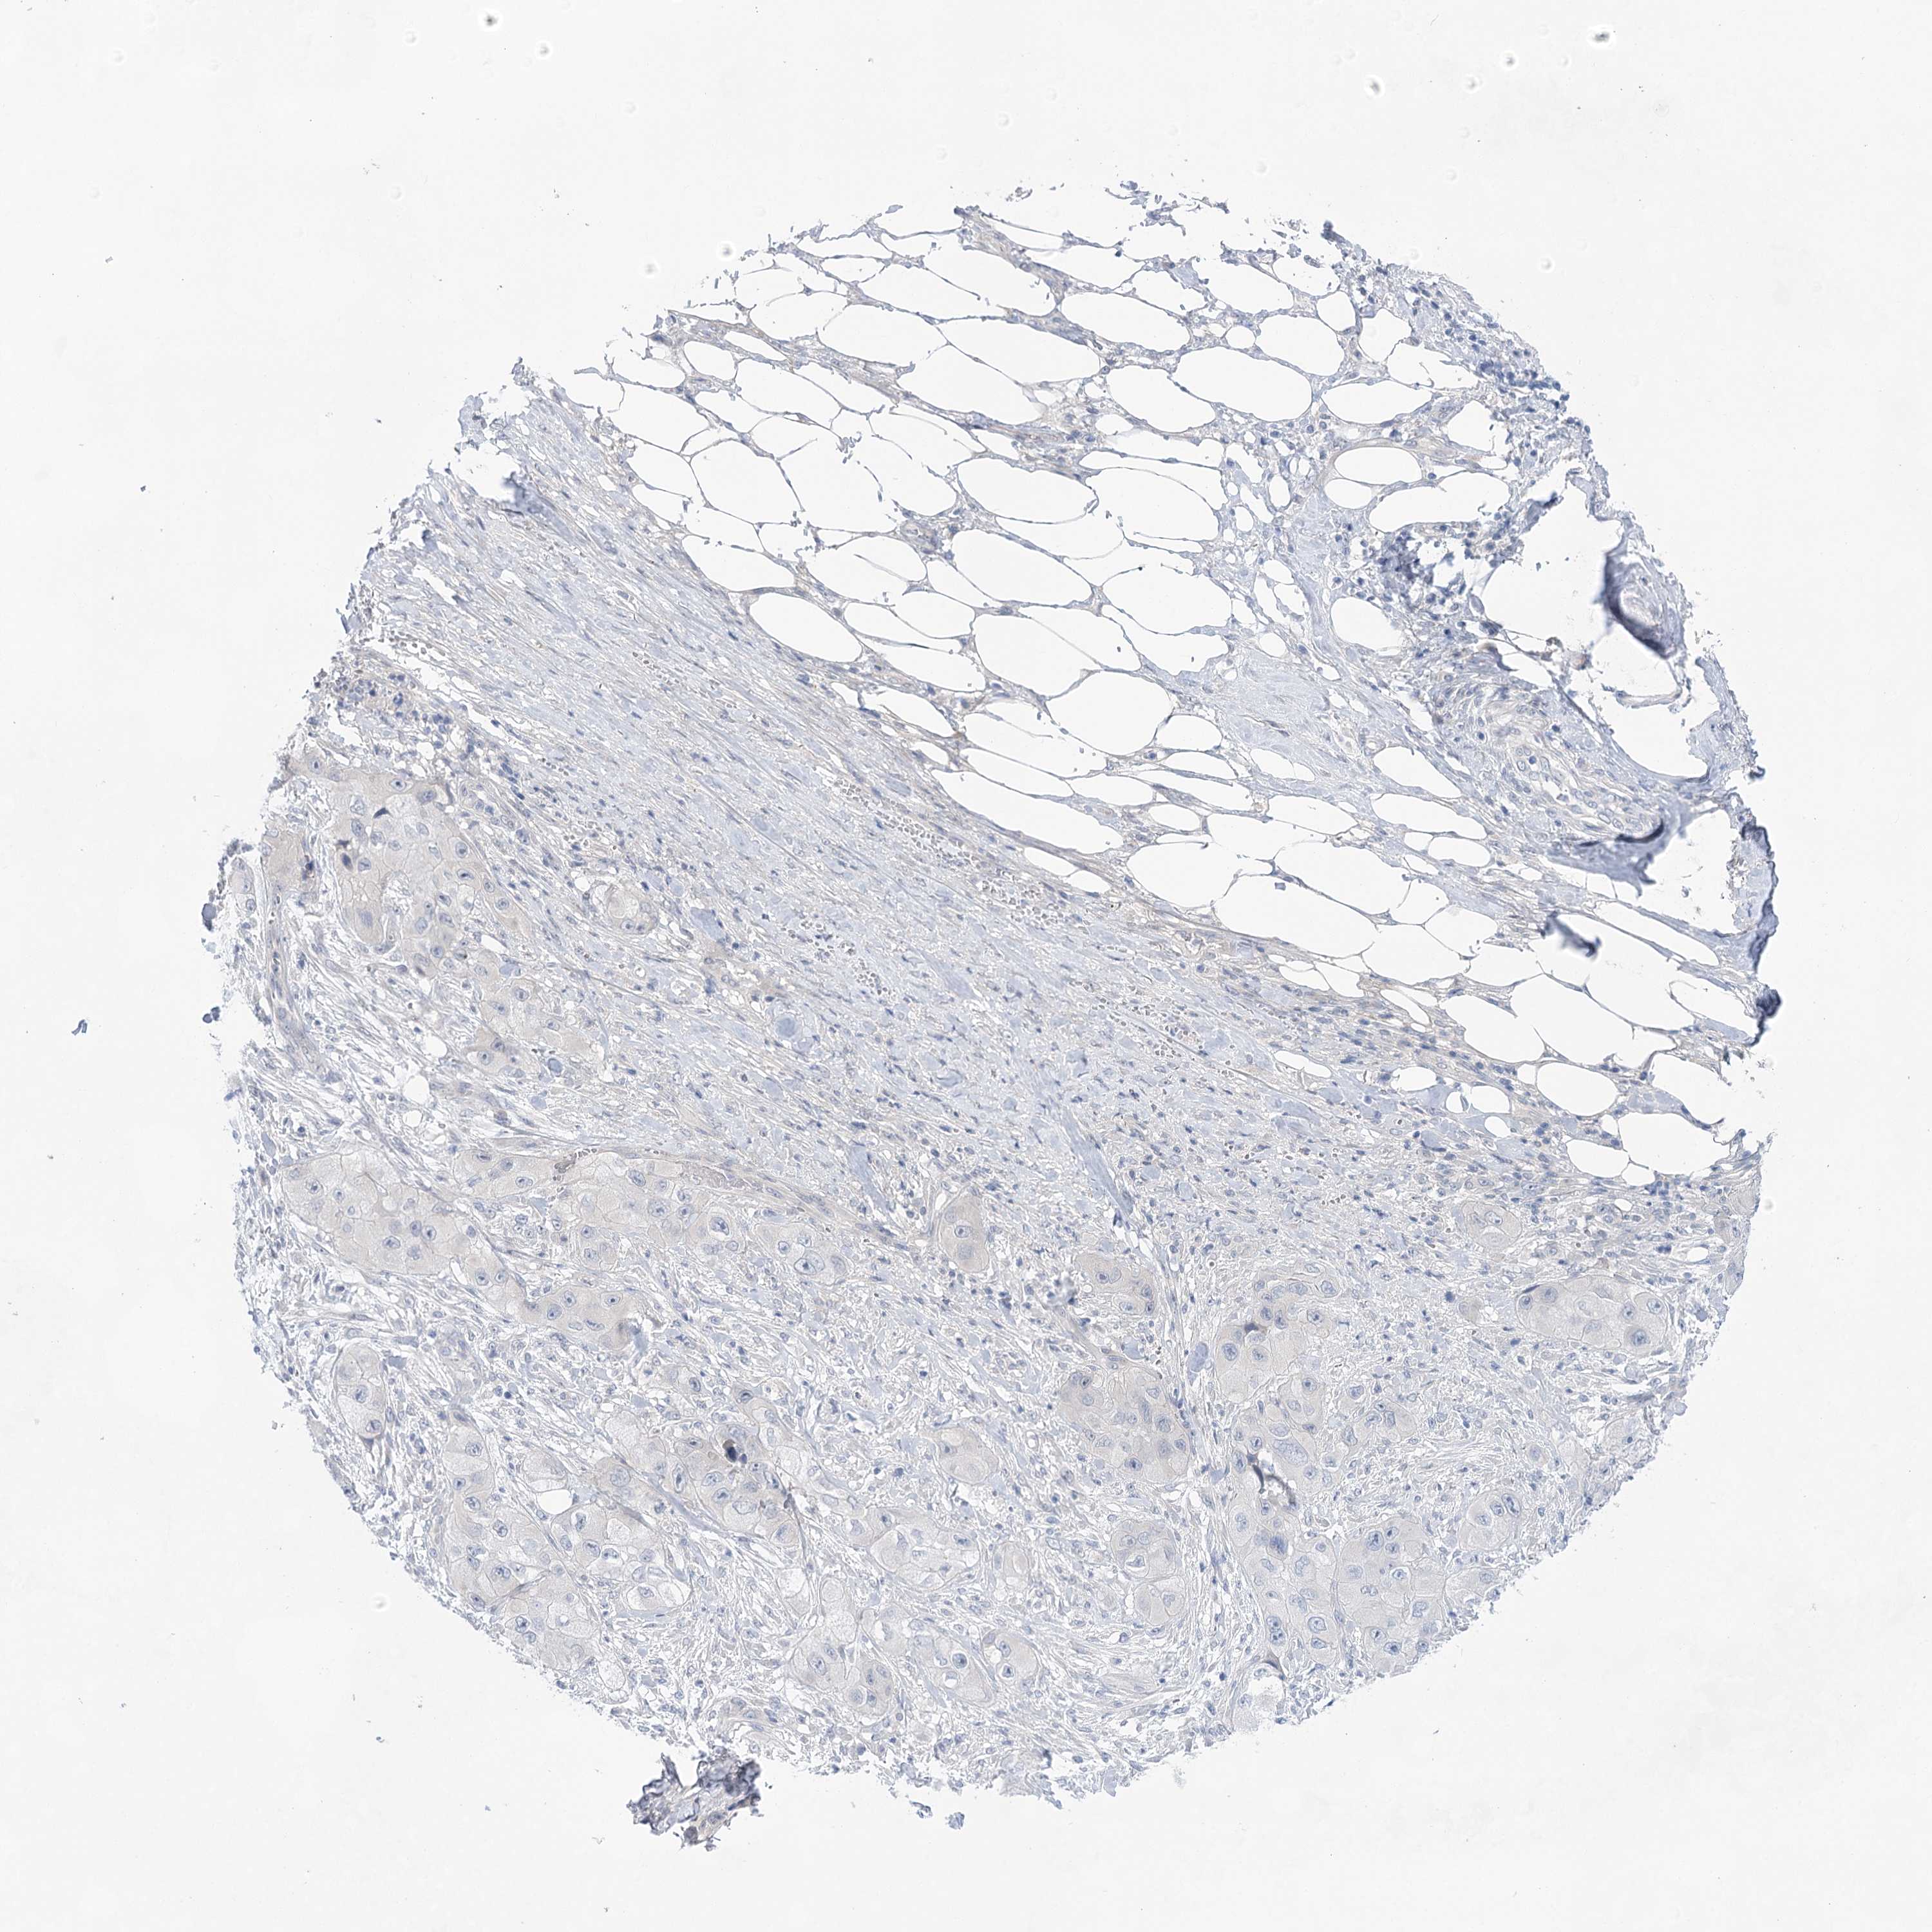

CANCER SKIN CANCER Show tissue menu

Basal cell and squamous cell cancer

SKIN CANCER - Protein expressioni

A mouse-over function shows sample information and annotation data. Click on an image to view it in a full screen mode. Samples can be filtered based on level of antibody staining by selecting one or several of the following categories: high, medium, low and not detected. The assay and annotation is described here.

Each image is clickable and will lead to virtual microscopy that enables deeper exploration of all samples and also displays staining intensity scores, fraction scores and subcellular localization as well as patient and tissue information for each sample.

Antibody HPA029855

Antibody HPA029856

Antibody CAB026343

Basal cell carcinoma

Squamous cell carcinoma, NOS

Squamous cell carcinoma, metastatic, NOS